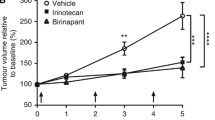

ROC analysis provided an optimal threshold to distinguish between viable and necrotic tissue, based on fractional enhancement (Fig. 5a). The upper threshold was 0.33 (i.e. voxels showing less than 33% signal enhancement on T1w imaging, after administration of gadolinium, were classified as necrotic). This threshold provided a sensitivity of 85% and specificity of 90% for identifying the ‘gold-standard’ necrotic tissue, with an AUC of 0.93.

a Receiver operator characteristics to determine a threshold which best separates necrotic and viable Wilms tumour tissue. The optimum upper threshold (0.33), whereby voxels displaying enhancement above this value are classified as viable, is highlighted in red. For this threshold, the area under the curve was 0.93, sensitivity was 85%, and the specificity was 90%. b Box and whisker plot displaying fractional enhancement of every voxel from the 37 Wilms tumours which were either classified as necrotic or viable. The dotted line reflects the optimum threshold (0.33 fractional enhancement) for this separation based on ROC analysis which is shown in (a)

Figure 5b displays a box and whisker plot of the fractional enhancement values in the manually defined necrotic and viable ROIs across the entire cohort. An independent sample T test revealed a significant difference between fractional enhancement values in the viable (mean, 0.73; SD, 0.33) and necrotic (mean, 0.14; SD, 0.2) voxels, t(195364) = − 446.96, p < 0.001. The optimum threshold (0.33) which separates necrotic and viable tumour tissue is also highlighted in Fig. 5b.